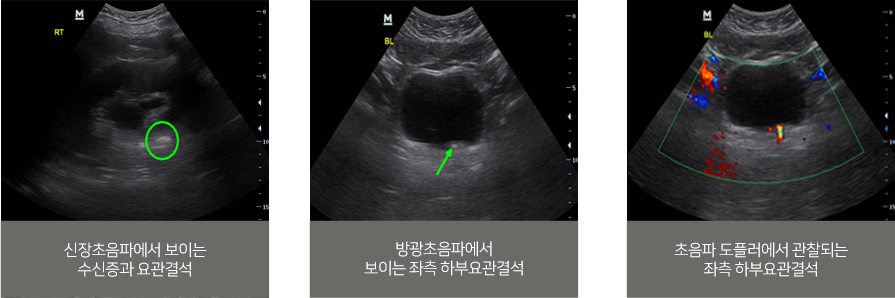

요로결석을 진단할 때는 증상과 병력 청취 후 추가적 정밀 검사 를 시행 후 요로결석에 대한 확진이 가능합니다.

초음파 검사[MINDRAY-DC-T6]